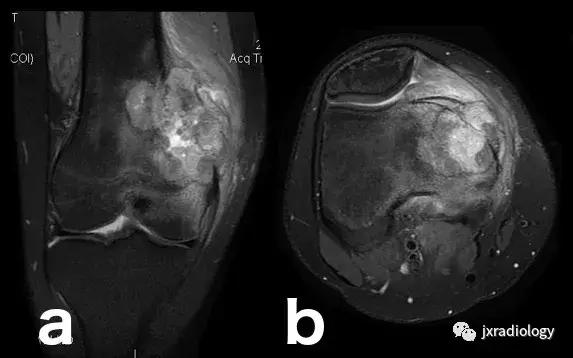

图22:骨肉瘤(a,b:冠状和轴向PD-FS-WI):肿瘤性水肿继发于骨小梁破坏引起的直接毛细血管损伤,并伴有血管内液体释放和出血。区分周围水肿和肿瘤侵袭可能是困难的。

图23:骨巨细胞瘤(PD-FS-WI):也存在肿瘤性骨髓水肿。